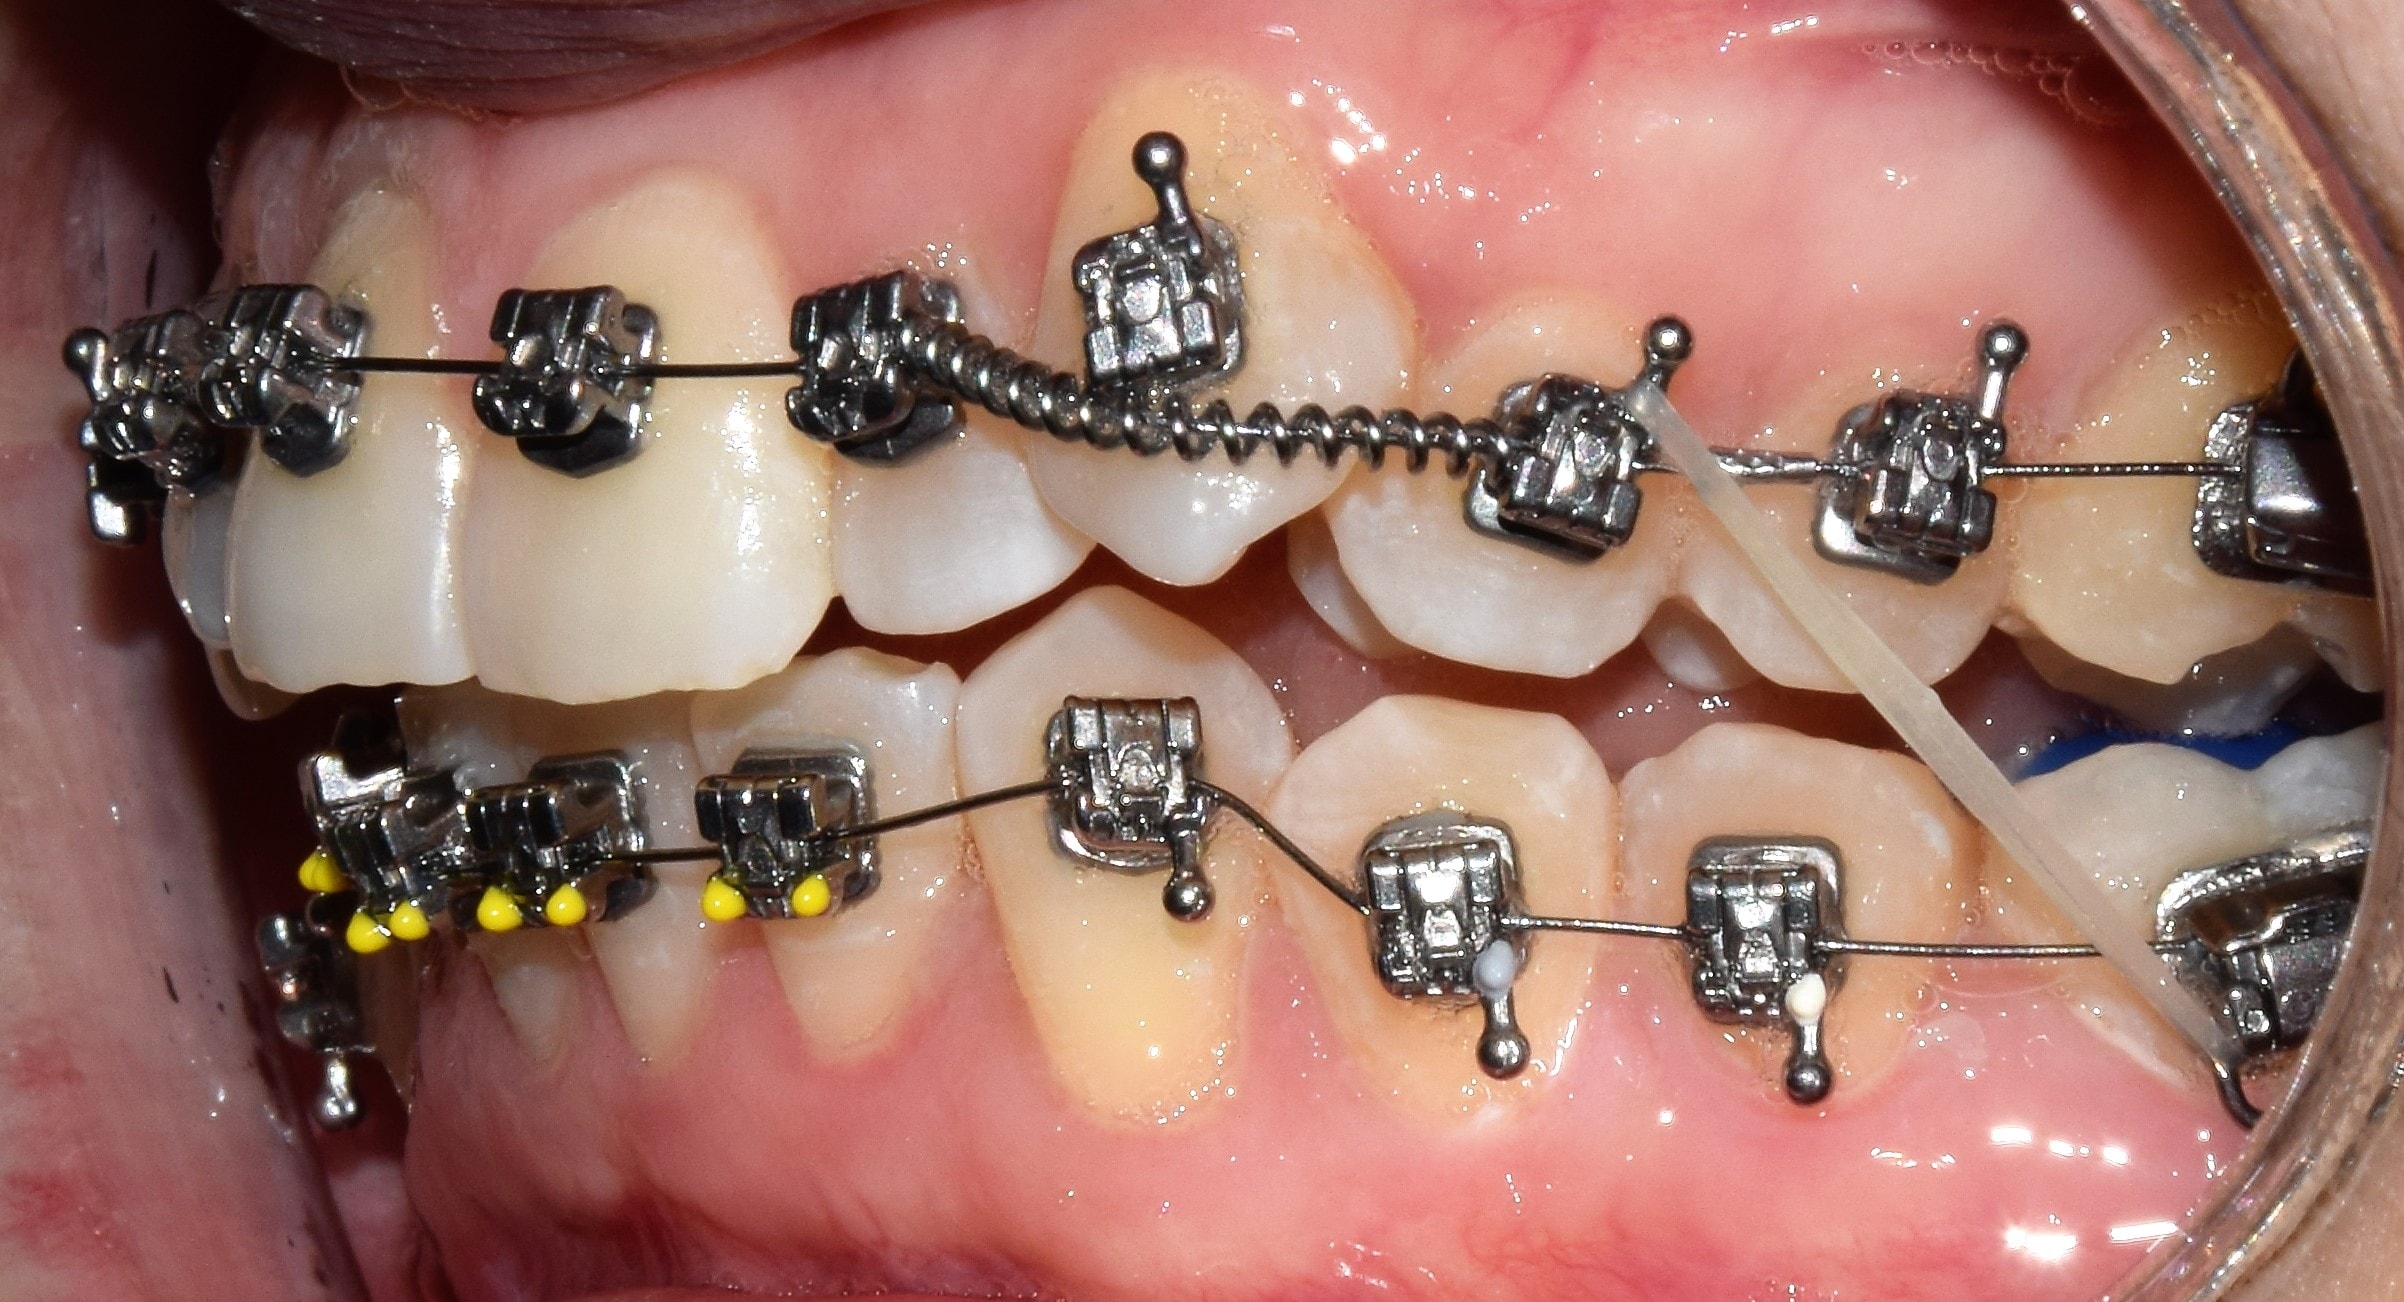

Fotódokumentáció

A fogszabályzó kezelés előtt-alatt-után rendszeresen készítünk fényképeket. Ez egy külön erre a célra összeállított tükörreflexes fényképezőgéppel történik. Nem a legkellemesebb élmény a fogszabályozás során, de utána nagyon jó lesz visszanézni a képeket. Sok fontos információt nyerhetek ki a készített fotókból, olyanokat is, amelyeket esetlegesen szájban nem veszek észre (nagyon kis méretűek), de egy nagy monitoron már könnyedén. A fotódokumentáció tehát még pontosabbá, precízebbé teszi a kezeléseim, és segít a maximum elérésében.